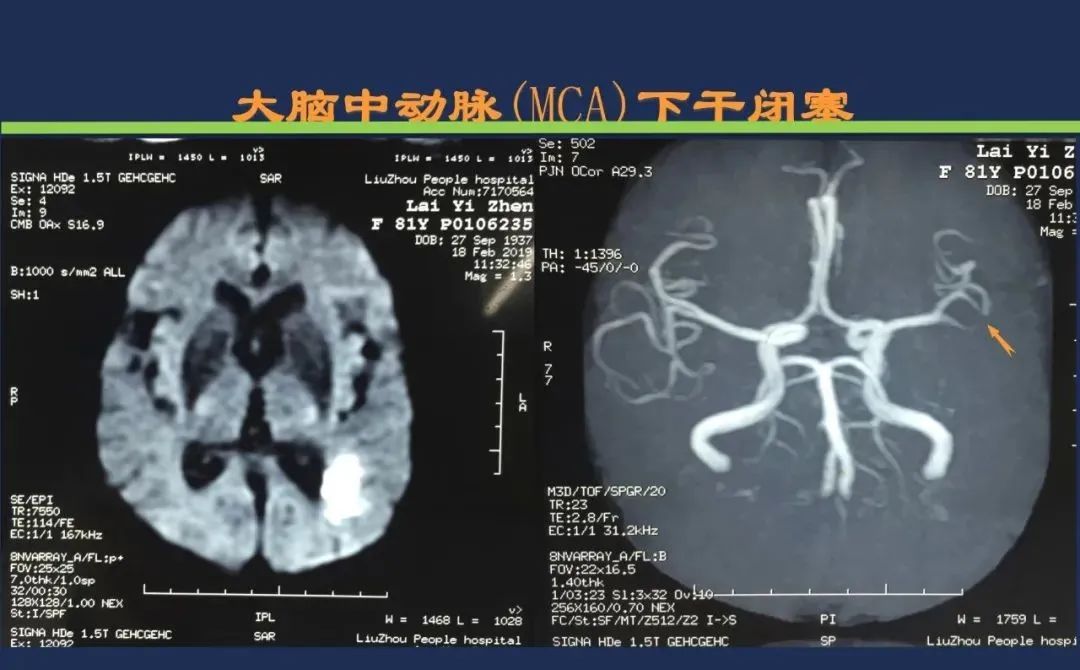

颈内动脉系统梗死颈内动脉大脑中动脉